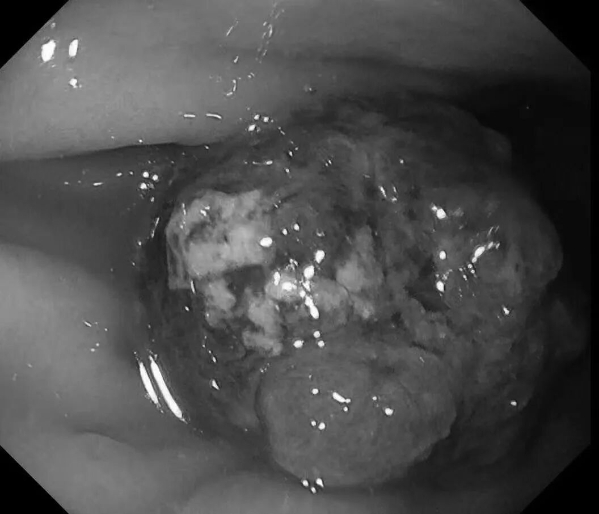

患者王阿姨(化名),65岁。平日里胃肠偶有轻微不适——腹胀,女儿考虑到母亲的年龄,想做个胃早癌筛查,遂带王阿姨来新镜界做胃肠镜精查。

检查中:胃体发现重要异常——胃体巨大息肉,直径约40x40mm!表面充血,带有亚蒂,未来有可能发展为胃癌,健康隐患极大!经与患者家属沟通同意,綦盛麟教授采用ESD(内镜下黏膜剥离术)成功切除巨大息肉。